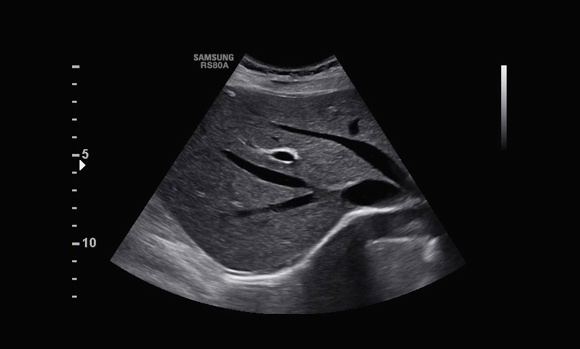

Gallbladder

Elevate your clients' experience with RS80A with Prestige